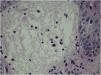

Two weeks after the cat had died, she developed a pustule on her thigh (Fig. 1A), treated with topical neomycin, which developed into an ecthymoid lesion (Fig. 1B). A few days later she started to develop disseminated lesions, with a pseudo-vesicular appearance (Fig. 2) accompanied by arthralgia, which made walking very difficult. With the suspicion of Sweet’s syndrome associated with sporotrichosis, given the history of exposure to the cat and no recent use of medications, oral itraconazole 100 mg/day and prednisone 40 mg/day were started. A culture was collected from the ecthymoid lesion, which was positive for Sporothrix spp. (Fig. 1C) and an inflammatory lesion on the back was biopsied. On histopathology there was marked edema in the superficial dermis associated with a lymphocytic and neutrophilic infiltrate and a extravasation of red blood cells. There was no spongiosis or vacuolar damage (Figs. 3 and 4).